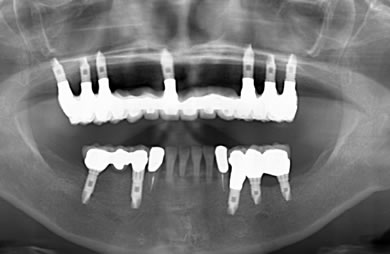

骨再生スピードインプラント治療+AGC連結セラミック治療

| 治療方針 | 上顎の歯周組織がかなり侵襲されているため、ソケットリフト法にて骨を回復させ、機能的回復だけでなく審美的回復も行うためにAGCハイブリッド連結ブリッジにて補綴処置を行う。 | ||||||||||||||||||||||||||||||||

| 治療内容 | インプラント12本(ソケットリフト+抜歯即日スピードインプラント)、ハイブリッドセラミック8本、AGCハイブリッドセラミック連結ブリッジ1装置、テンポラリーインプラント2本、遊離歯肉移植術 | ||||||||||||||||||||||||||||||||